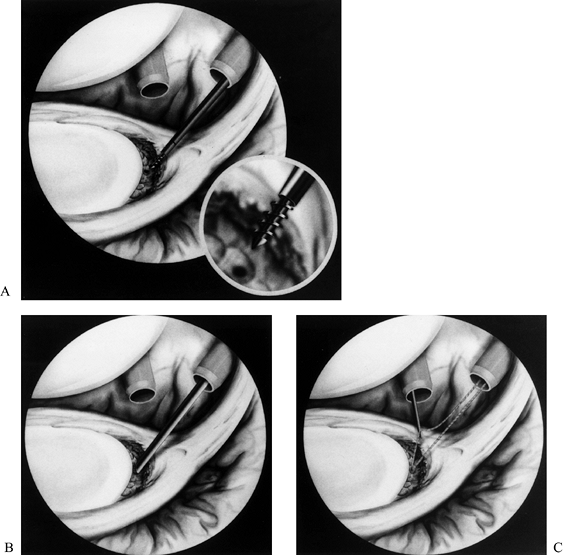

![]() |

|

Figure 80.3.

Arthroscopic view through a posterior portal demonstrates an anatomic variant of the anterior glenoid labrum referred to as a sublabral hole. This should not be confused with a true Bankart lesion or a superior labrum anterior posterior (SLAP) lesion. (From Warner JJP, Warren RF. Arthroscopic Bankart Repair Using a Cannulated Absorbable Fixation Device. Oper Tech Orthop 1991;1:192, with permission.) |